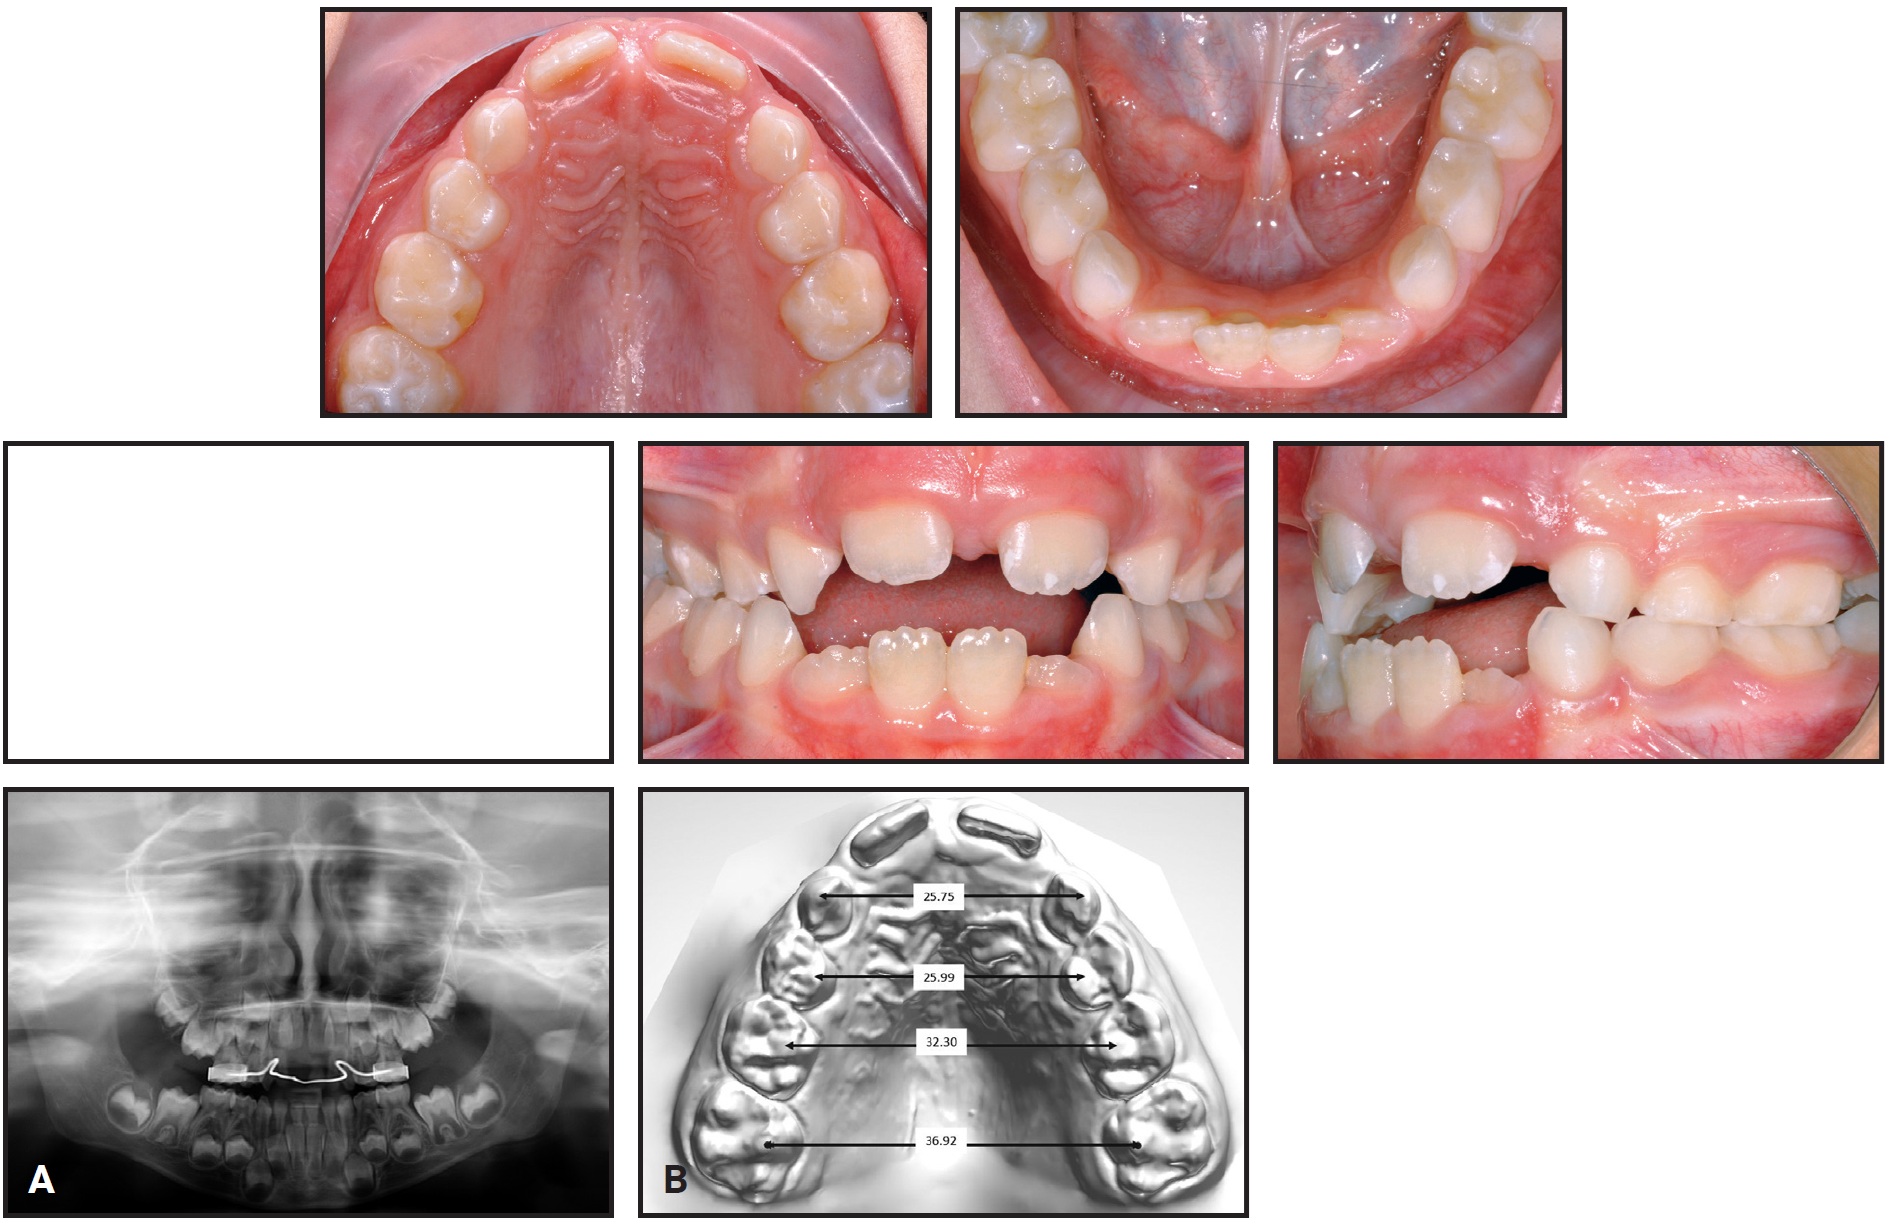

A 6-year-old male in the mixed dentition presented with a lack of space for his lateral incisors and a crossbite associated with a lateral mandibular shift to the right and a transverse discrepancy (Fig. 3, Table 1). The upper right central incisor had been extracted following an intrusive trauma at age 4; the space had been maintained with a transpalatal arch and composite pontic.

Fig. 3 Case 1. A. 6-year-old male patient with maxillary transverse deficiency, crossbite, mandibular deviation, and missing upper right central incisor (extracted at age 4) before treatment. (Panoramic radiograph taken seven months earlier.) B. Arch-width measurements on STL digital cast obtained from laboratory scan of polyvinyl siloxane impressions.